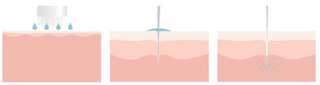

Microneedling significantly increases the transepidermal penetration of drug substances. Can be combined with other medicalcosmetic techniques to deliver better results. A very safe technique for all types of skin.

Microneedling is a minimally invasive technique that creates thousands of epidermal microcanals that allow substances to pass through the horny layer of the skin, while simultaneously producing dermoepidermal biostimulation, incrementing the activity of the drug substances.

Dose the c.prof or x.prof solution on a defined and localised area, simultaneously applying the microneedling technique with m.pen[pro] and adjusting the device's depth.

In vivo histological view showing the microcanals formed with the microneedling technique.